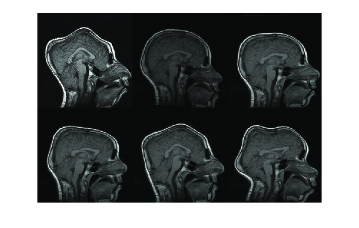

Figure 7: Resulting registration of images with random affine warps. Each row includes source, target and registered source

Refer to caption

In Figure 7, three example registration results of randomly and affinely warped images are shown. The resulting images clearly show that registered source images are in good agreement with target images. Registration quality is measured over 30 randomly deformed images by mean of the square of the differences in intensity (MSE). Experiment has been done both in image scale and on standard scale to show improvement in MSE sense. Table-1 shows the MSE, maximum MSE and minimum MSE over 30 registration examples on image scale and on intensity scale respectively.

In Figure 9, three example registration results of randomly and nonlinearly warped images are shown. Capturing signal intensity variations during registration process with intensity standardization method leads to assesment of visual comparision of registered source and target images with warping grid. Evaluation of the registration results is summarized in Table-2. The table shows that large and small scale deformations are captured accurately on the standard intensity scale. Resulting images have fixed intensity meanings even there is large intensity variations initially.

Figure 9: Resulting registration of images with random nonlinear warps. Each row includes source, target, registered source and estimated warping grid